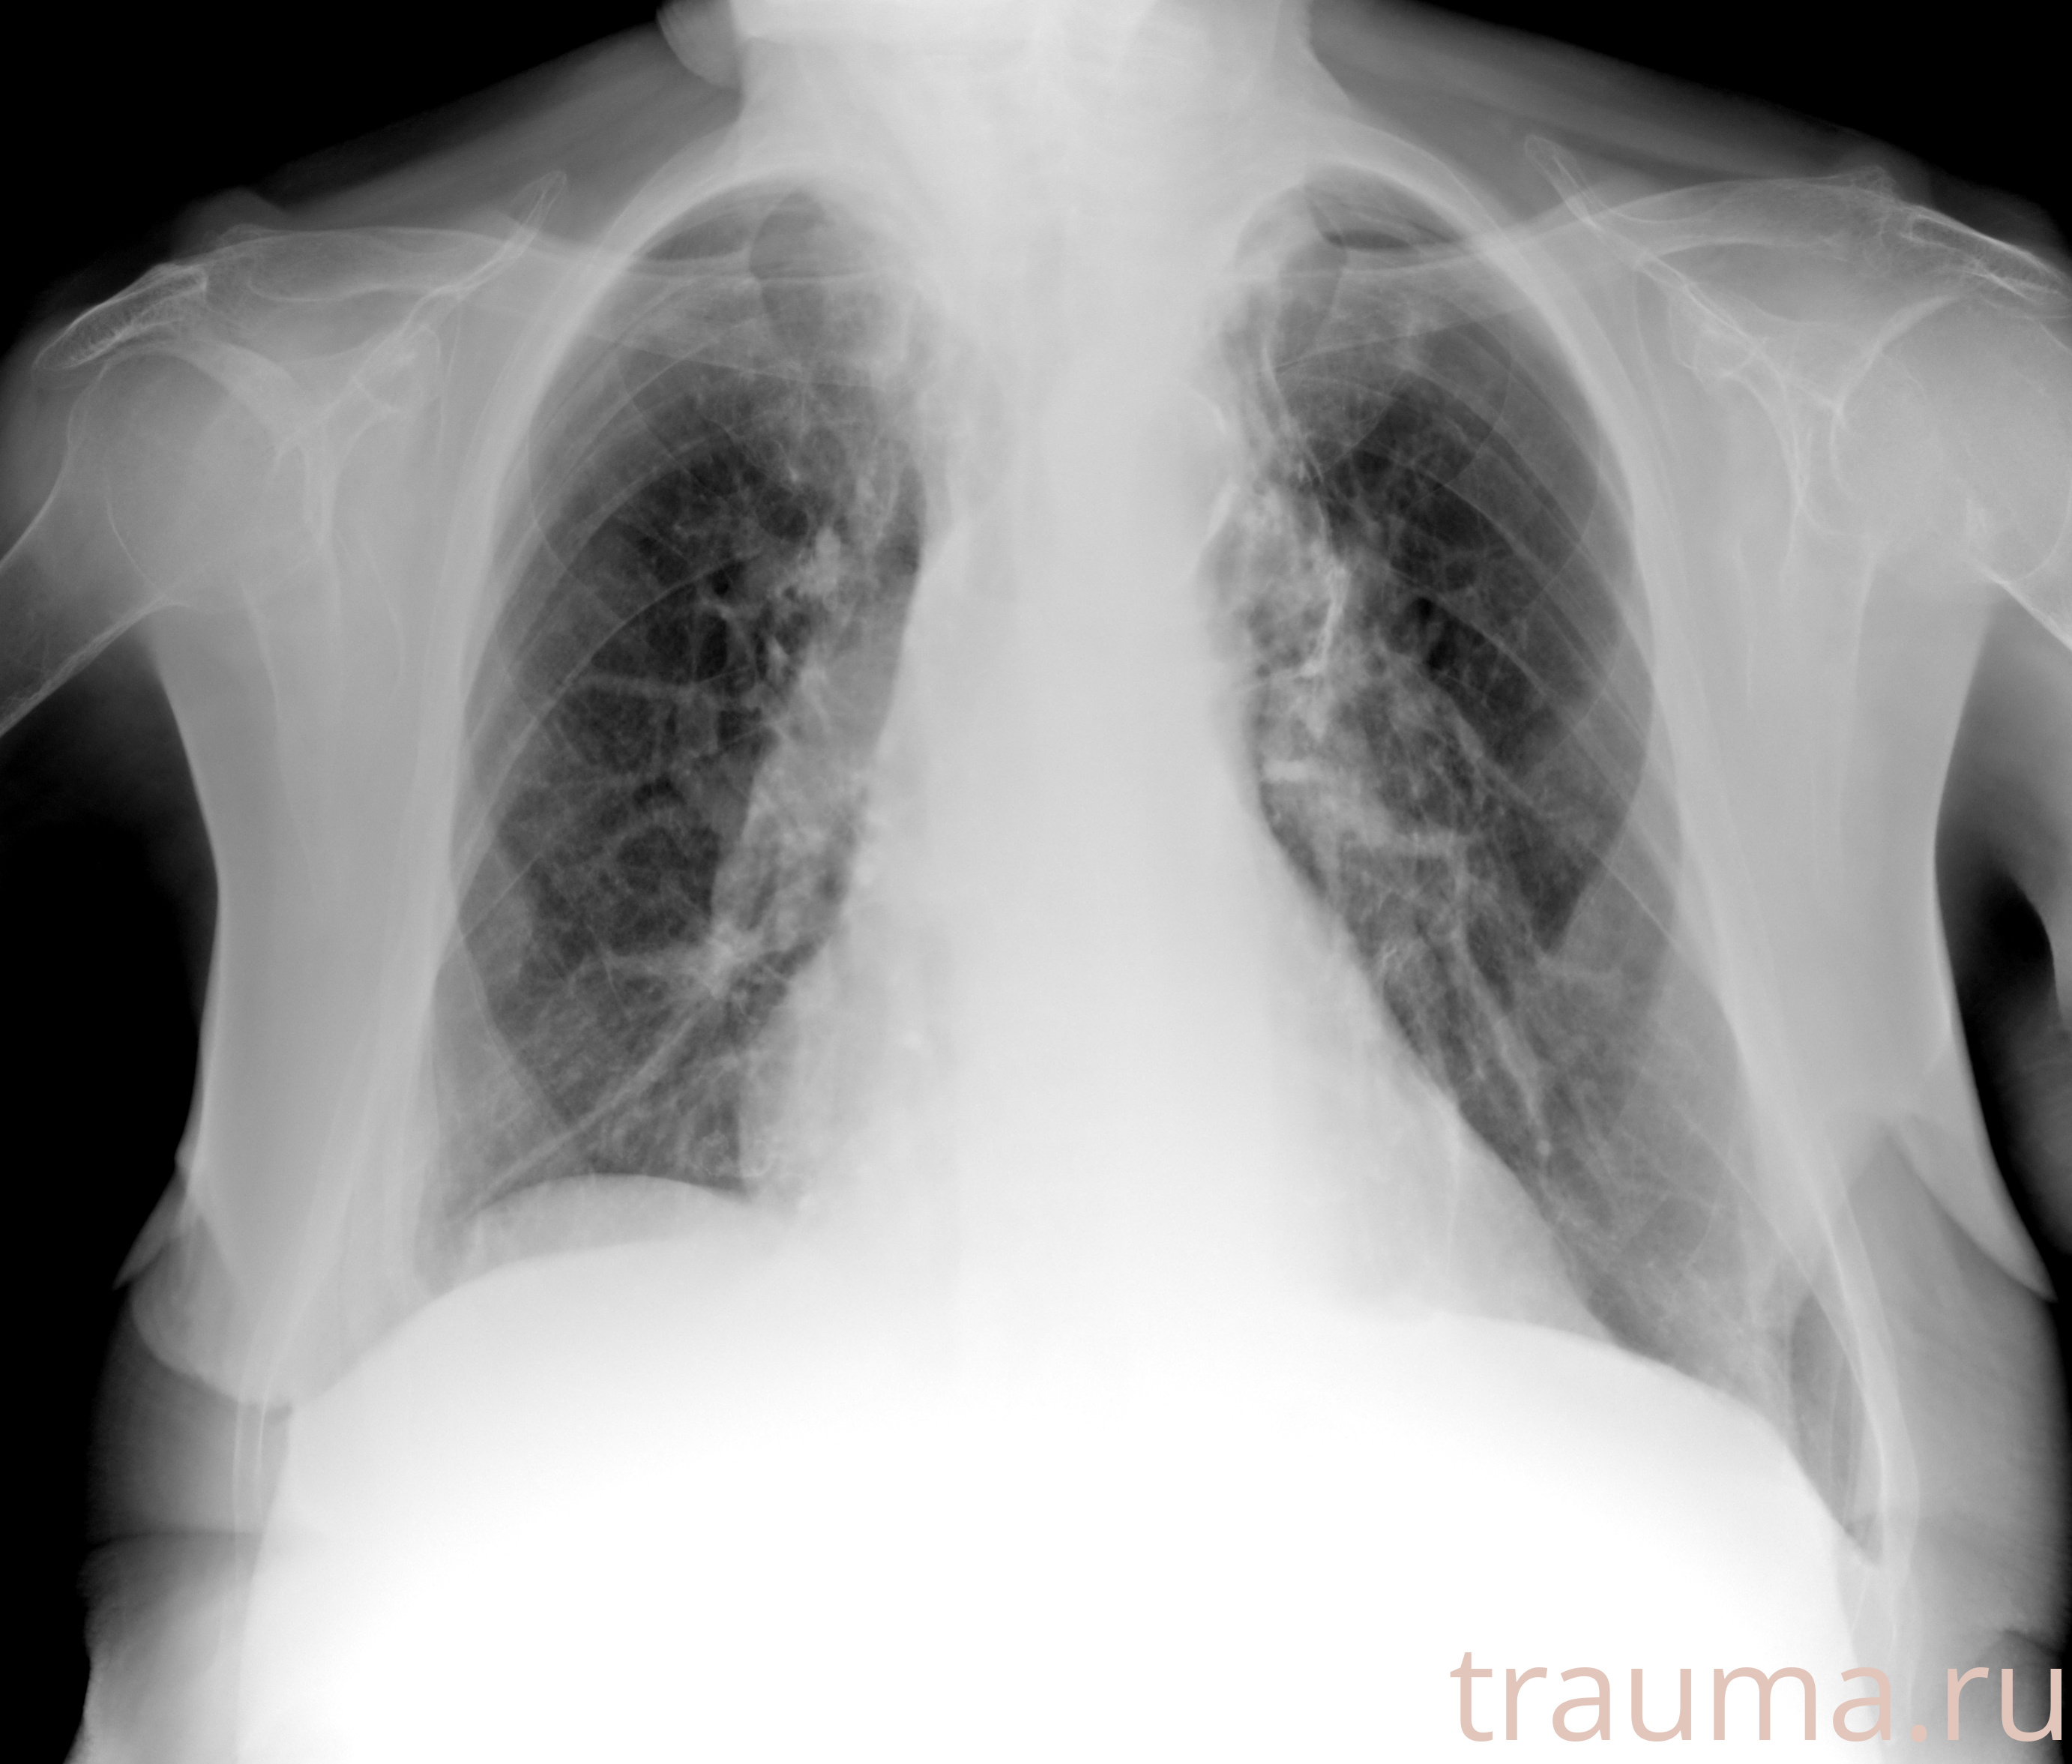

Рентгенограммы

Рентген на дому: по вашему адресу приезжает врач-рентгенолог, травматолог-ортопед с мобильным рентгеновским аппаратом, проводит диагностику травмы или заболевания, делает необходимые рентгенограммы, дает рекомендации по дальнейшему лечению. Получить качественные снимки в домашних условиях возможно благодаря уникальной методике, разработанной МосРентген Центром для института  Склифосовского

Яркость: 1   Контраст: 1   Инвертировать: 0 Увеличение: 1

Перетаскивайте мышь вверх/вниз для контраста, влево/право для яркости. Прокрутка колесом изменяет масштаб. Нажмите Сбросить для возврата к исходному изображению. При увеличении держите мышь в той области, которую хотите рассмотреть.